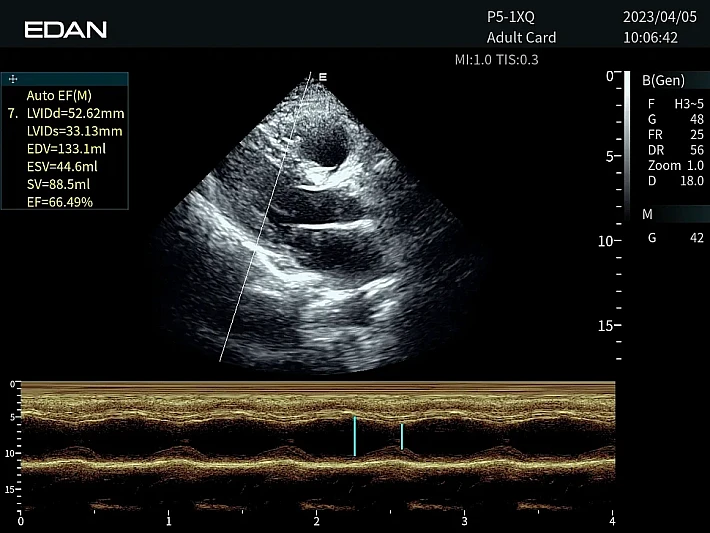

Медицинское оборудование и сервисное обслуживание